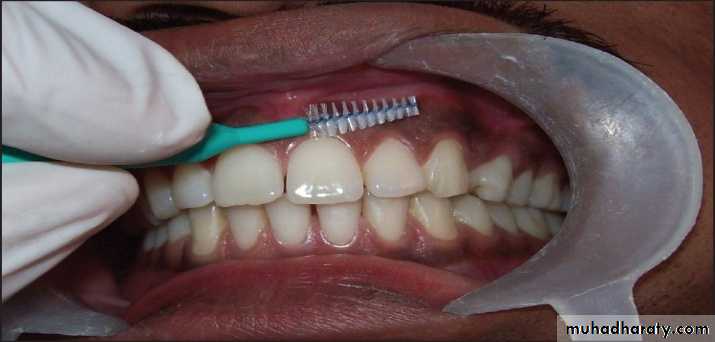

gingivectomy: surgical excision of unattached gingival tissue.gingivoplasty: surgical recountour of the gingival

tissues.Frenectomy(surgical removal or resectioning of a frenum): surgery that may be performed on the maxillary labial frenum to correct diastema(a space between two teeth), or on the mandibular lingual frenum to correct ankyloglossia